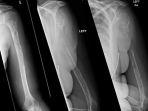

Diet Rendah Kalori berdampak pada tulang

Jika Anda Melakukan Hal ini Ada Dampak Buruk yang Akan Terjadi Pada Tulangmu